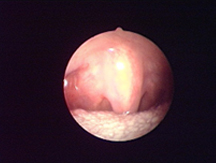

適應于凝血和組織的收縮。

適用于良好控制的止血。

適合于要求良好止血的切割。